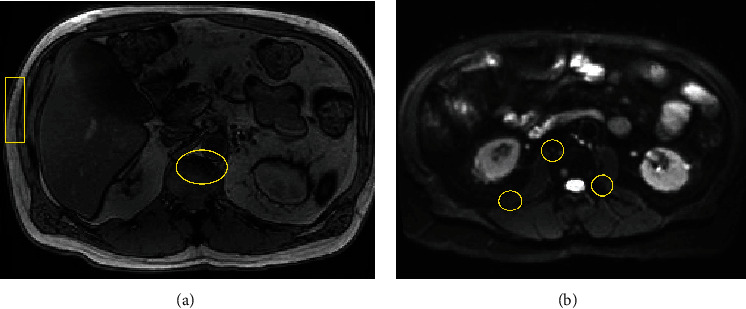

Chronic lymphocytic leukemia (CLL) typically presents as an indolent disease with a benign disposition in most patients. In select patients, CLL can progress into a more aggressive disease via its original morphology, following a Richter transformation to an alternative non-Hodgkin's lymphoma, or with the concomitant development of multiple myeloma. In an extremely rare subset of individuals with CLL, an extramedullary plasmacytoma may coexist. This case report seeks to describe the diagnosis and treatment of a patient with concurrent CLL and a plasmacytoma.